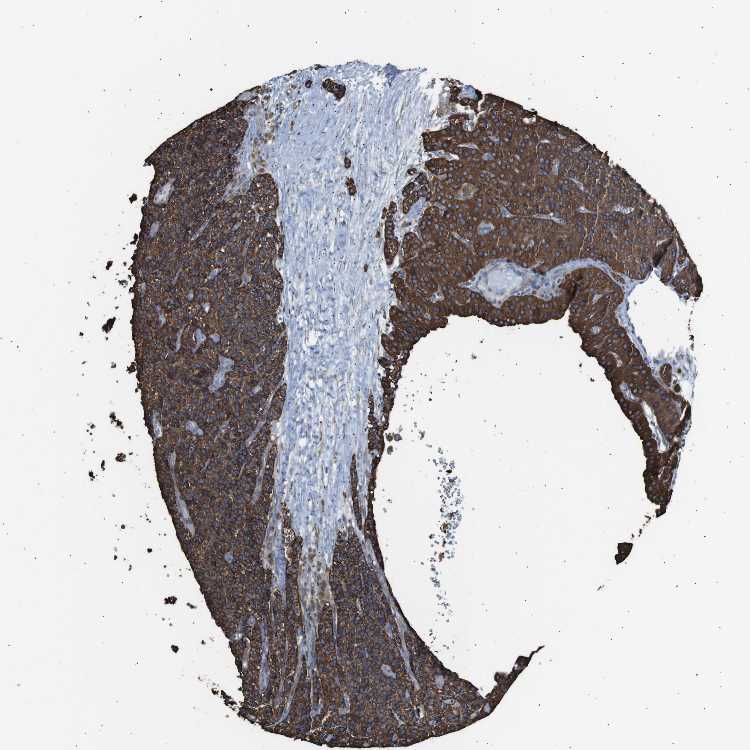

TISSUE PRIMARY DATA PARATHYROID GLAND Show tissue menu

PARATHYROID GLAND - Antibody stainingi

Antibody staining in the annotated cell types in the current human tissue is reported as not detected, low, medium, or high, based on conventional immunohistochemistry profiling in selected tissues. This score is based on the combination of the staining intensity and fraction of stained cells.

Each image is clickable and will lead to virtual microscopy that enables deeper exploration of all samples and also displays staining intensity scores, fraction scores and subcellular localization as well as patient and tissue information for each sample.

Antibody HPA015914

Glandular cells High